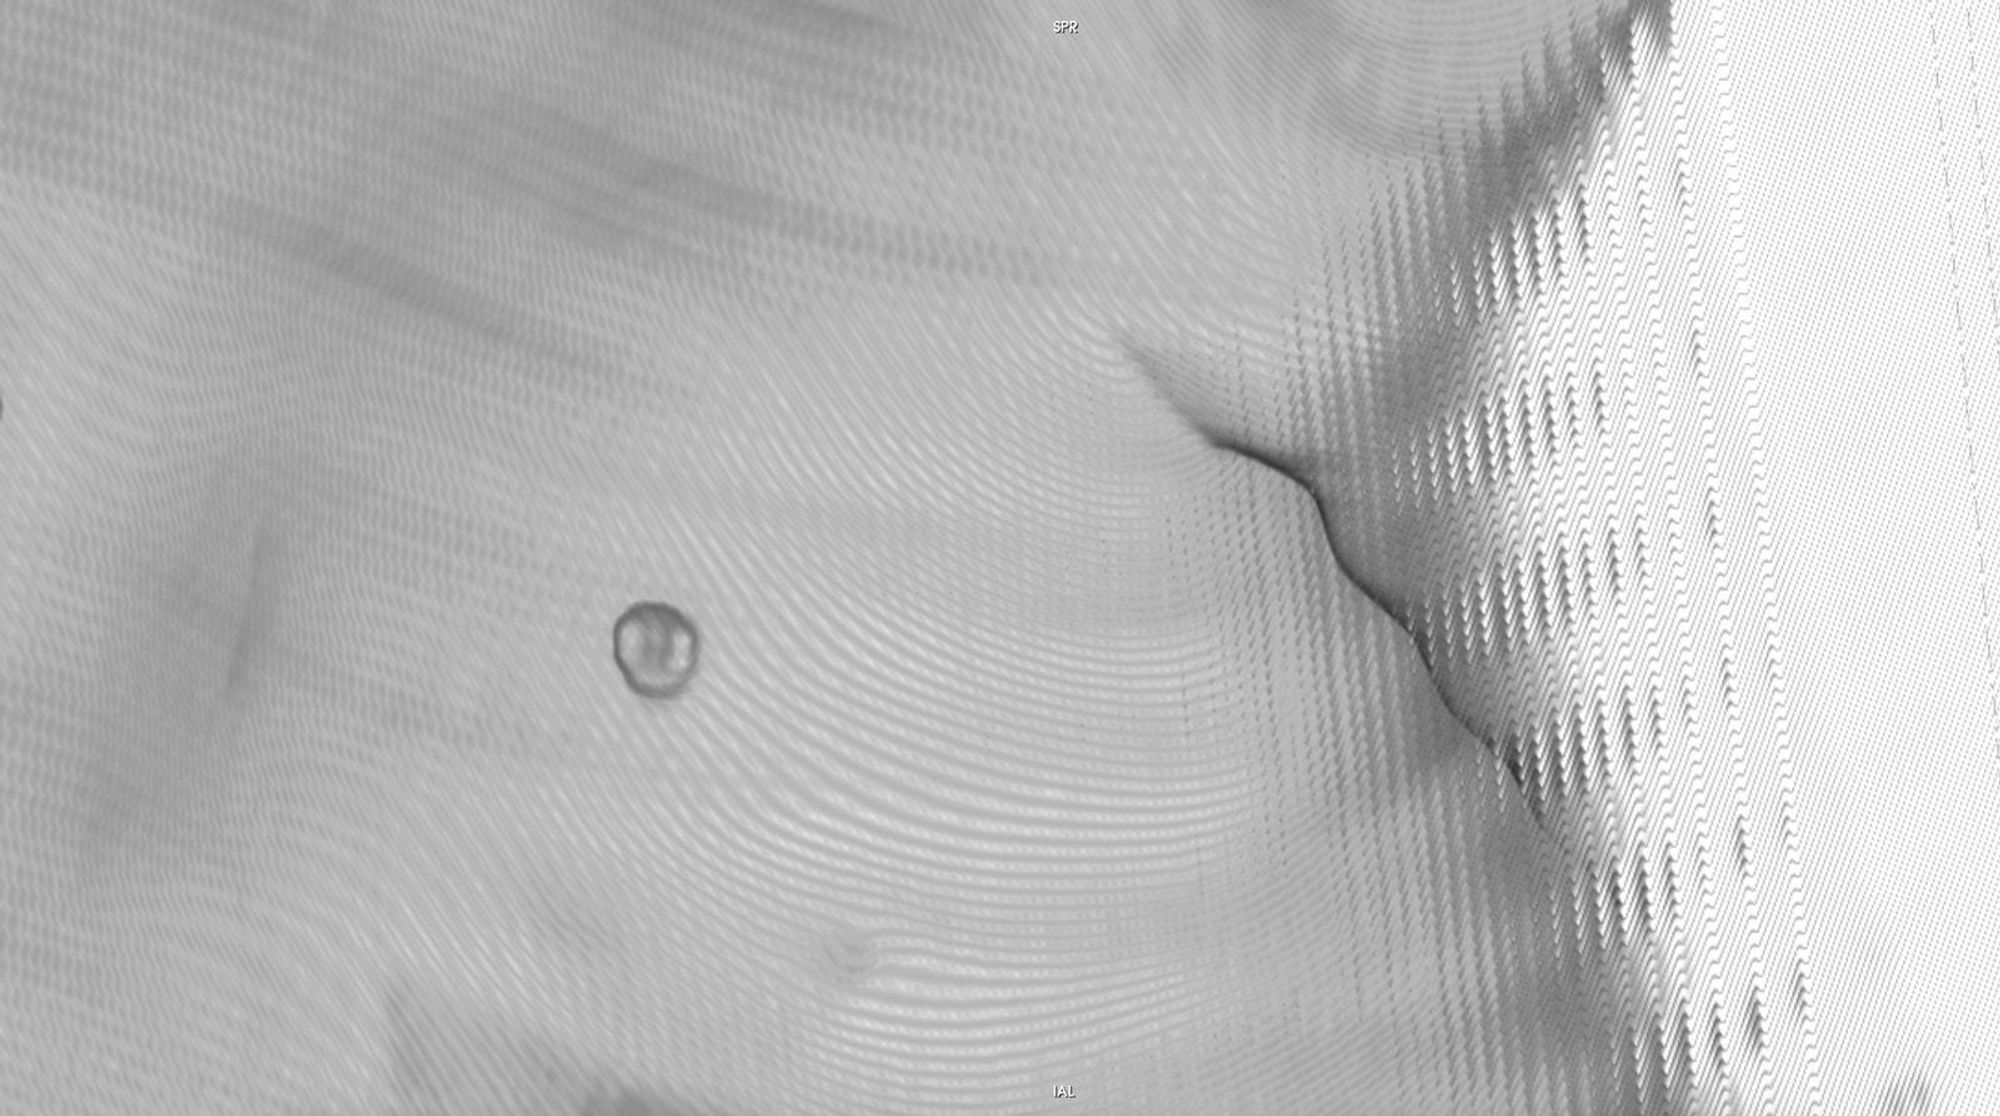

Chasing Intensities considers the body through its relationship to contemporary medical imaging technologies.

In this project, I look at the visual limit between the inside and the outside, the inner and the outer. I combine different visual approaches to materialise the body, using medical imagery, photography from manuals and radiology software. Decontextualised from their origin, these images speak of medicine’s relationship to both sex and violence, and remind us that, in medicine, to go into the body is always to go into the image first.